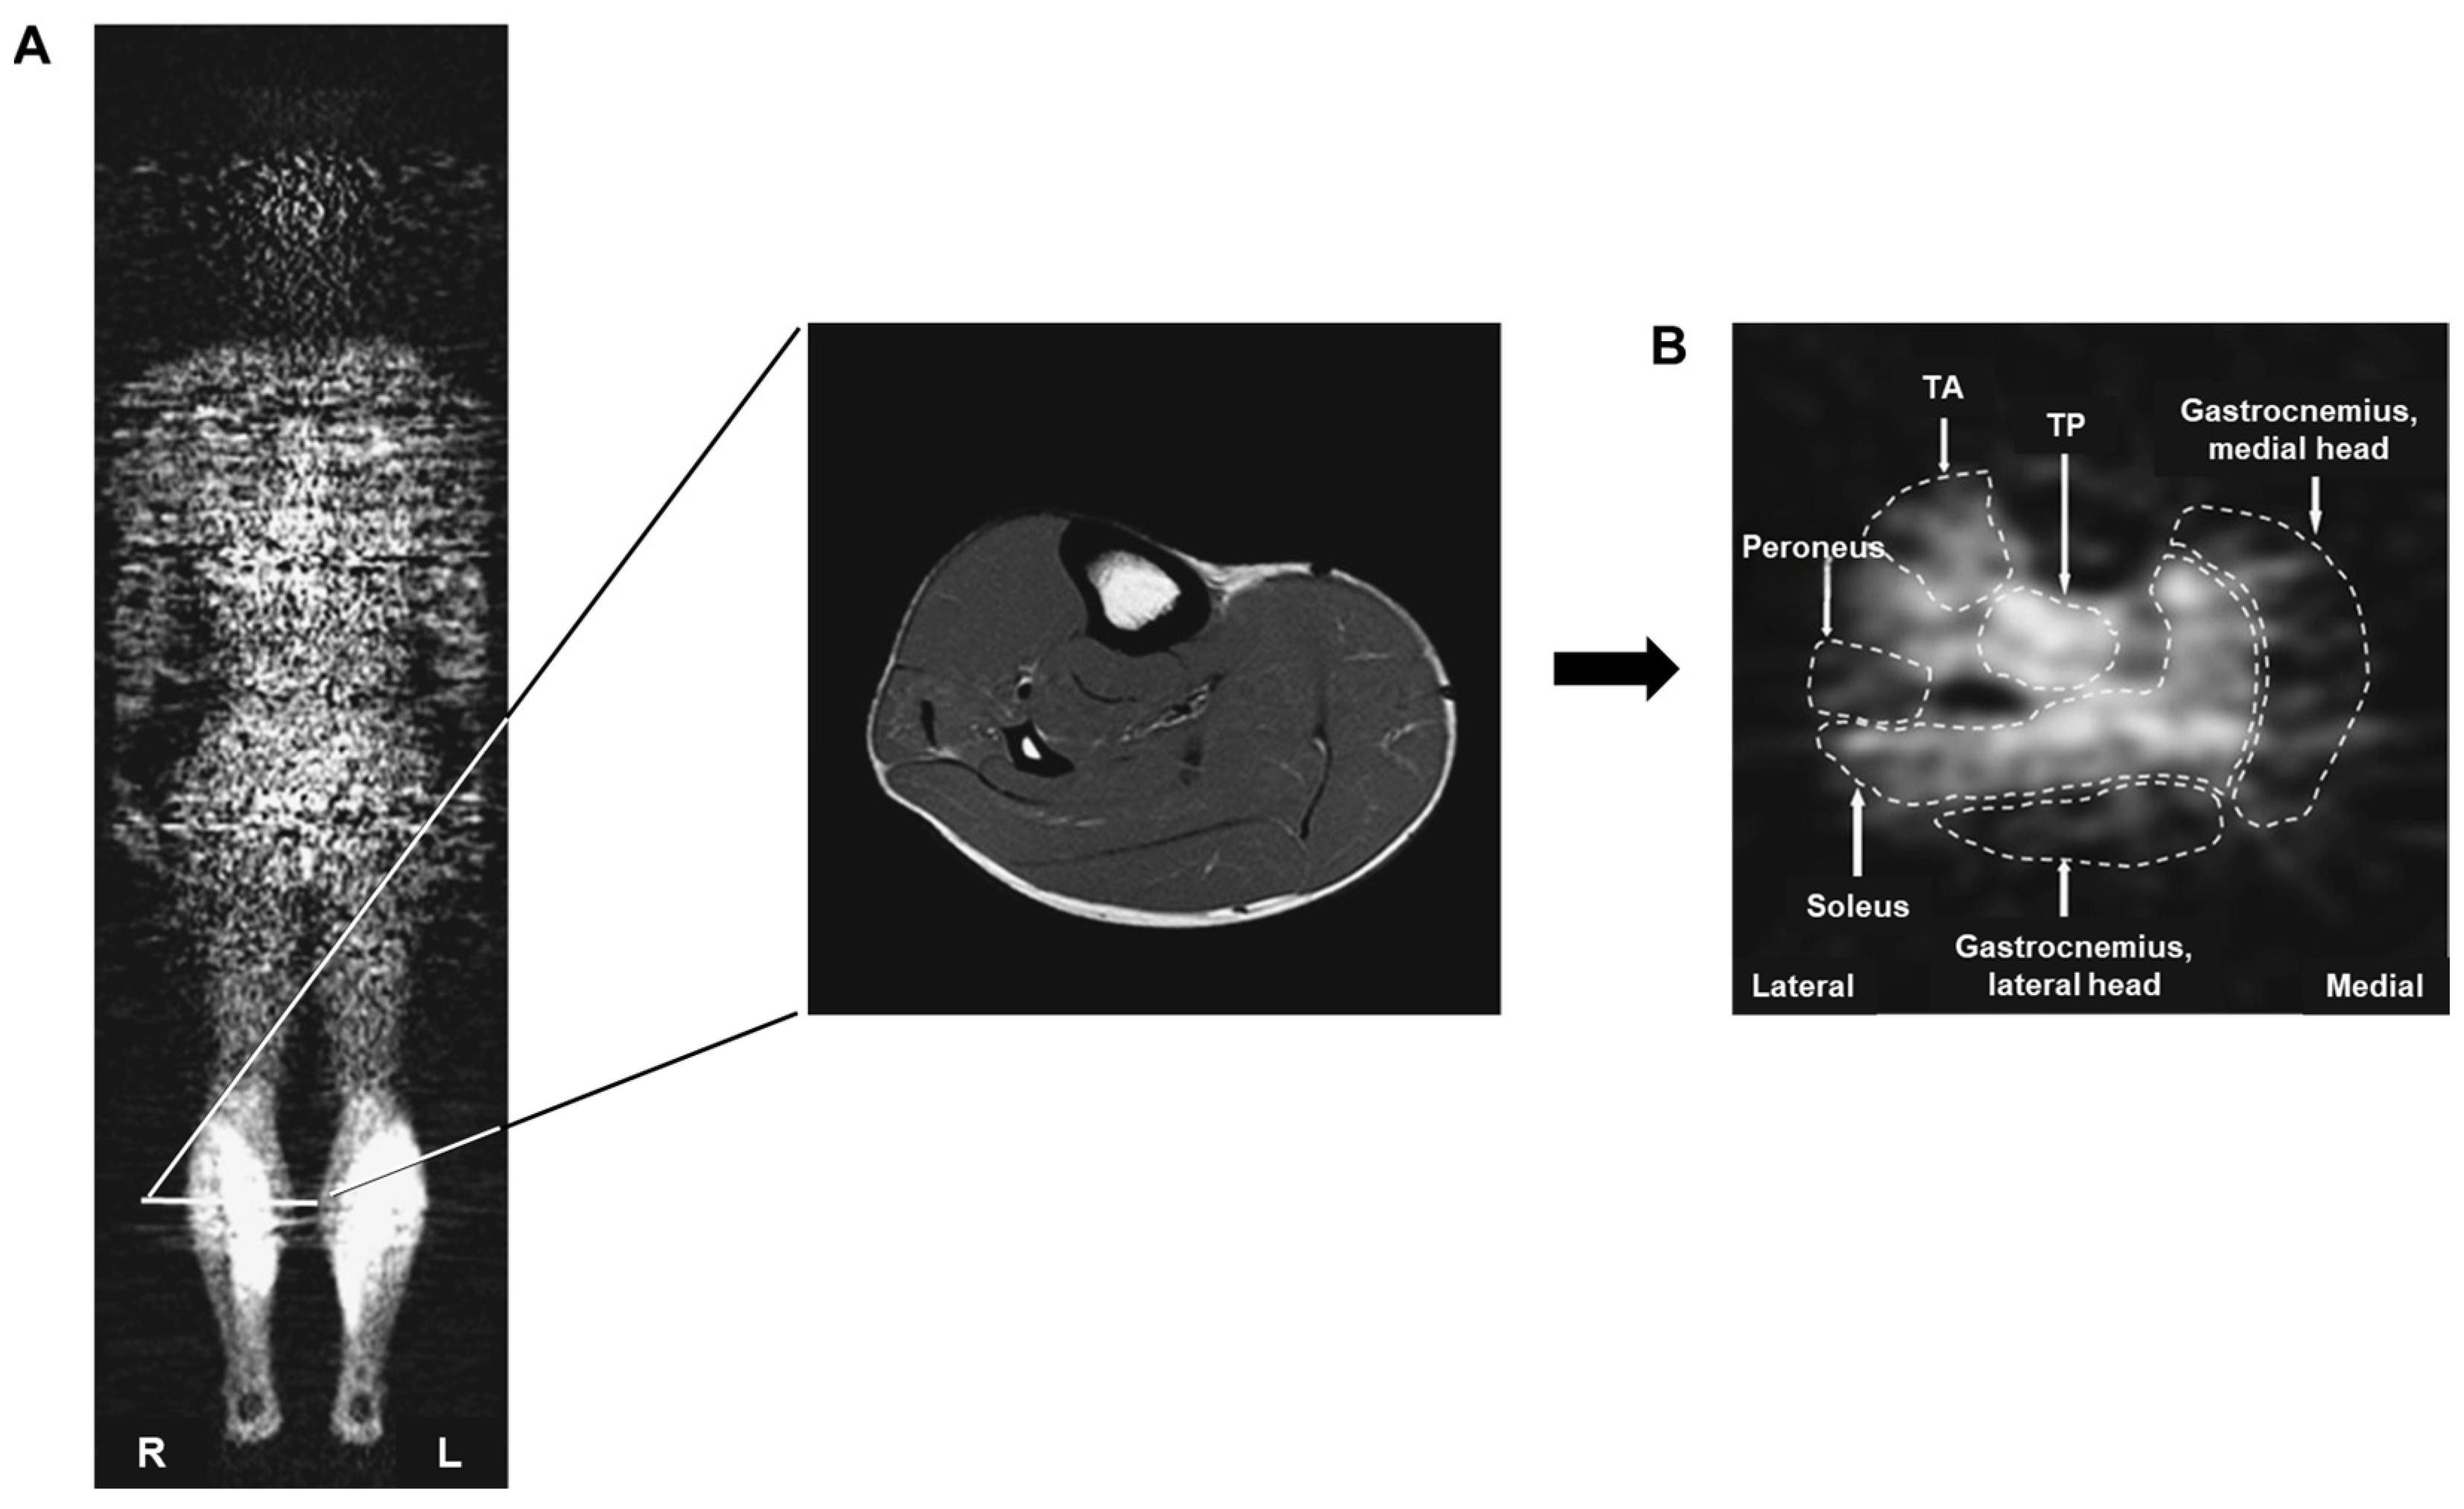

- Kolk, S.; Klawer, E.; Visser, E.; Lobeek, D.; Schepers, J.; Verdonschot, N.; Weerdesteyn, V. Symmetry and spatial distribution of muscle glucose uptake in the lower limbs during walking measured using FDG-PET. PLoS ONE 2019, 14, e0215276. [Google Scholar] [CrossRef]